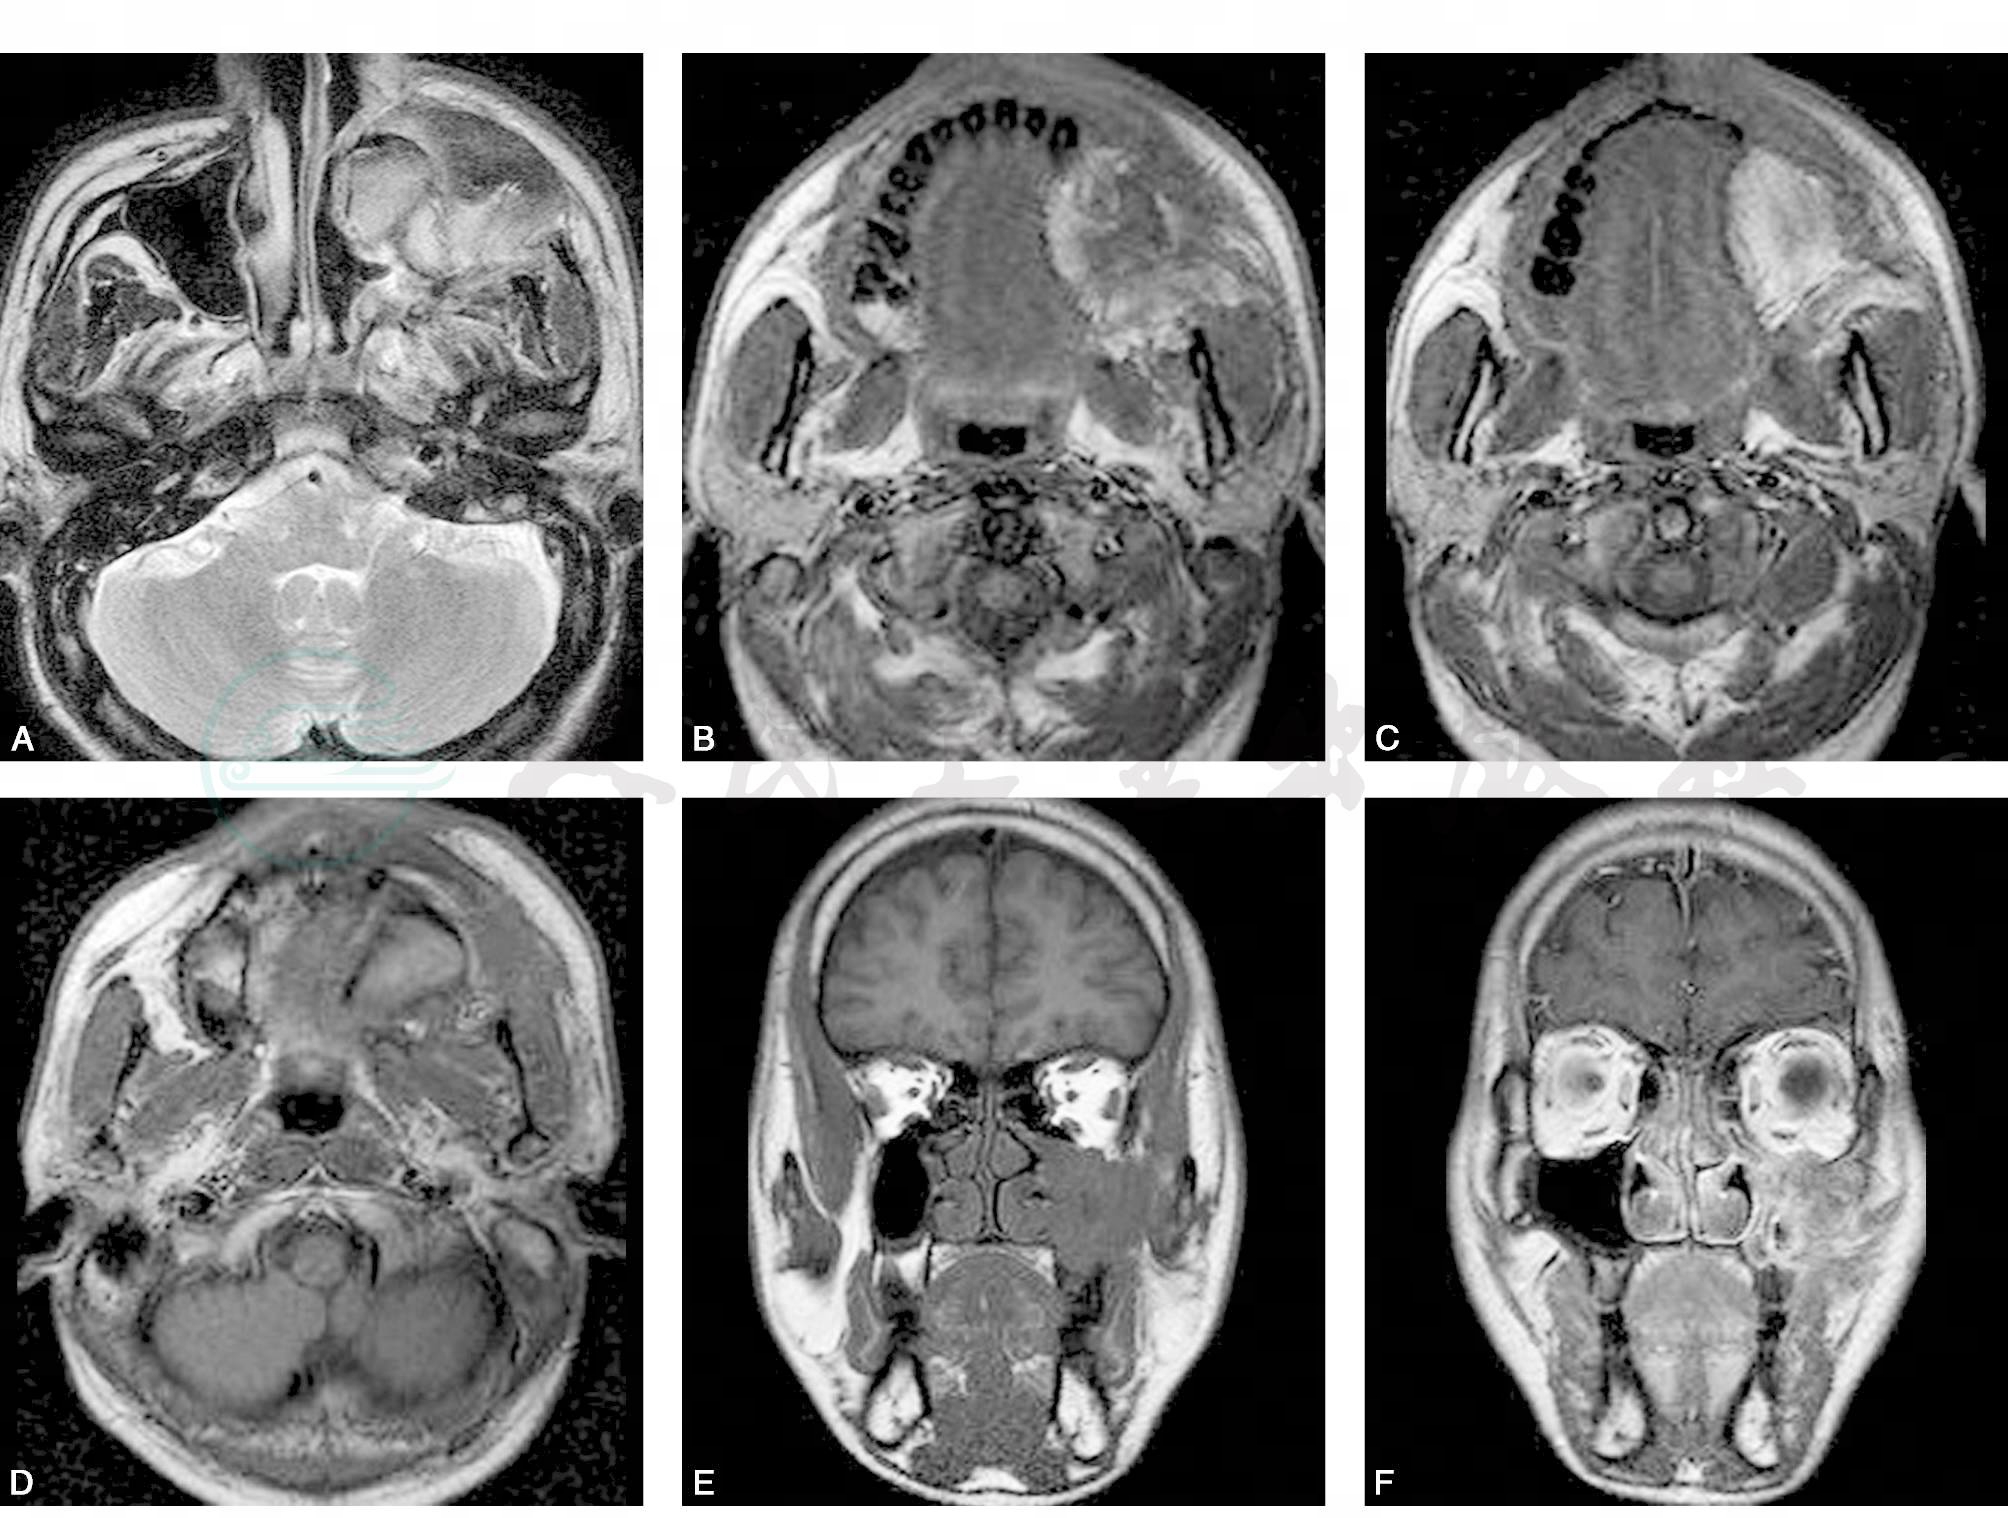

左侧上颌窦腔内填充软组织肿块,T2WI图像上呈等、稍高信号(图1A),T1W图像上呈等、稍高信号(图1B~E),增强后肿块中度不均匀强化(图1F~H);左侧眶下壁、上颌窦前、后及内侧壁不同程度骨质破坏,肿块向前侵及左面部皮下软组织,向后侵及翼腭窝,左眶内下缘见少许软组织影,眼球及附属组织未见异常信号。左侧乳突气房减少,部分气房内黏膜增厚;颅底结构未见异常。诊断:①左侧上颌窦软组织肿块,考虑恶性肿瘤;侵及上颌窦骨壁及翼腭窝。②左侧乳突炎症。

图1 上颌窦恶性纤维组织细胞瘤

A. T2W横断面;B. T1W横断面:C. T1W横断面;D. T1W横断面;E. T1W冠状面;F. T1W增强冠状面;G. T1W增强横断面;H. T1W增强横断面;I. HE×200